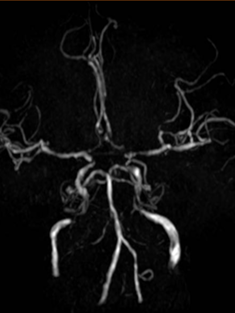

2022-02-05 颅脑MR。

导丝怎么扩【载药时代 球扩天下】NOVA DES®颅内药物洗脱支架在颈内动脉颅内段重度狭窄的应用二例!_https://www.jmylbn.com_新闻资讯_第23张

DWI

导丝怎么扩【载药时代 球扩天下】NOVA DES®颅内药物洗脱支架在颈内动脉颅内段重度狭窄的应用二例!_https://www.jmylbn.com_新闻资讯_第24张

MRA

重要影像结论:左侧额顶枕叶梗死灶。